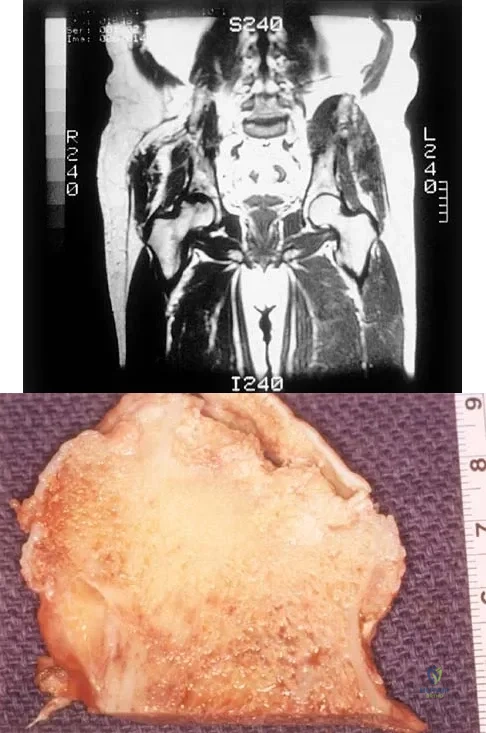

A 35-year-old patient has right hip pain. Figures 34a and 34b show the coronal MRI scan and the biopsy specimen. What is the most likely diagnosis?

Explanation